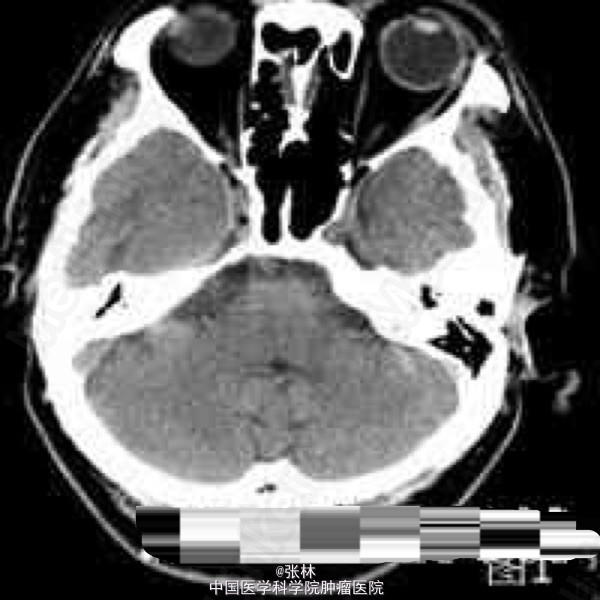

CT表现:右侧颅中窝可见一不规则肿块,呈等密度,内部密度均匀,CT值约37HU,肿块边界尚清晰,略成分叶状,与邻近骨质呈广基底相连,最大截面3.3cm×3.8cm,边缘处可见带状低密度影,边界清晰,CT值约16HU。肿块周边脑组织水肿,密度略减低。肿块周边骨质未见增厚硬化或变薄等异常改变(图1-2)。 CT诊断:右侧颅中窝肿块,伴周围脑组织水肿,建议进一步检查。 MRI表现:右侧颅中窝可见一不规则肿块,最大截面3.6cm×4.1cm,肿块边界清晰,成分叶状,与邻近骨质呈广基底相连(图5-6),在T1WI上呈等信号,在T2WI上呈略高信号;肿块边缘可见不规则液性信号带,在T1WI上呈低信号,在T2WI上呈高信号,与脑组织分界清楚(图3-4);肿块前方颞叶部分脑组织可见片状异常信号,在T1WI上呈稍低信号,在T2WI上呈略高信号,边缘模糊(图3-4);注射对比剂后,肿块实性部分明显强化,并可见“脑膜尾征”,而液性信号带未见强化(图5-6),肿块前方颞叶的片状异常信号未见强化。 MRI诊断:右侧颅中窝脑膜瘤,部分囊变,伴周围脑组织水肿。 手术病理结果:非典型性脑膜瘤,WHO分级II级。 讨论: 脑膜瘤是颅内仅次于胶质瘤的常见原发肿瘤,发病率占颅内肿瘤的16%~17%,在颅内脑外原发肿瘤中占第一位。它起源于脑膜的蛛网膜内皮细胞,常见于富含蛛网膜颗粒与蛛网膜绒毛的地方,以上矢状窦旁、大脑凸面、大脑镰、蝶骨嵴、鞍结节、嗅沟、小脑桥脑角区及小脑幕等部位多见。